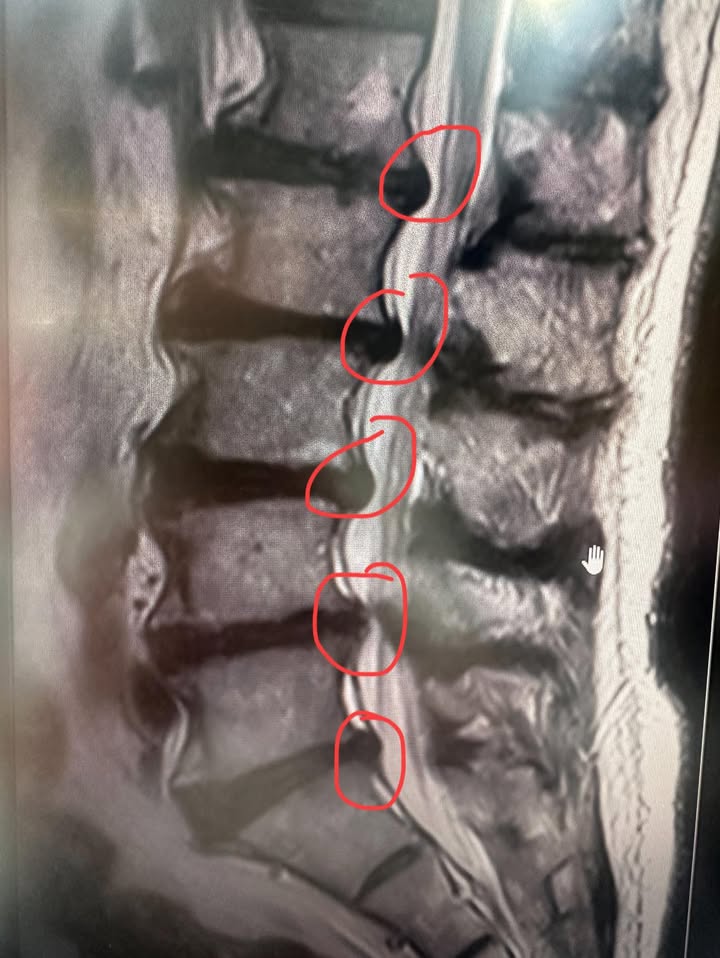

🟥MRI診斷判讀結果(結論):

1. 腰椎退化性關節炎併椎間盤脫水。

2. 椎體結節:第11節椎體0.52公分,第12節椎體0.71公分,及第1節椎體1公分,並伴有異常信號(T1WI和T2WI)

3. 雙側L1/L2節椎間盤中央旁突起,導致中央管狹窄及輕度的雙側L1神經孔狹窄。

4. L2/3節椎間盤基底寬大突起,導致中央管狹窄及輕度雙側L2神經孔狹窄。

5. L3/4、L4/5及L5/S1節椎間盤基底寬大突起,導致中央管狹窄及雙側L3神經孔狹窄,右側L4神經孔狹窄,及雙側L5神經孔狹窄。

結論:三節椎間孔連續狹窄真的很難治療。